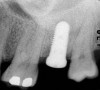

A round bur is usually used to mark the position where a 2-mm twist drill will be applied (Figure 1). Then the twist drill is employed to penetrate the cortical and trabecular bone (Figure 2). This provides information with respect to cortical bone thickness and medullary trabecular bone density. The amount of bone debris found on the twist drill can be interpreted as an indicator of bone quality (eg, the less debris and a more bloody appearance means softer bone). Four types of mineralized bone have been described by Misch (Table 1):1,2

Tactile feedback from the 2-mm twist drill clearly facilitates differentiating between D1 and D4 bone; however, it is difficult to distinguish between the intermediate classes of bone quality (D2 and D3).3 Nevertheless, the amount of cortical bone at the crest determined with the twist drill can provide valuable information (Table 1).1,2